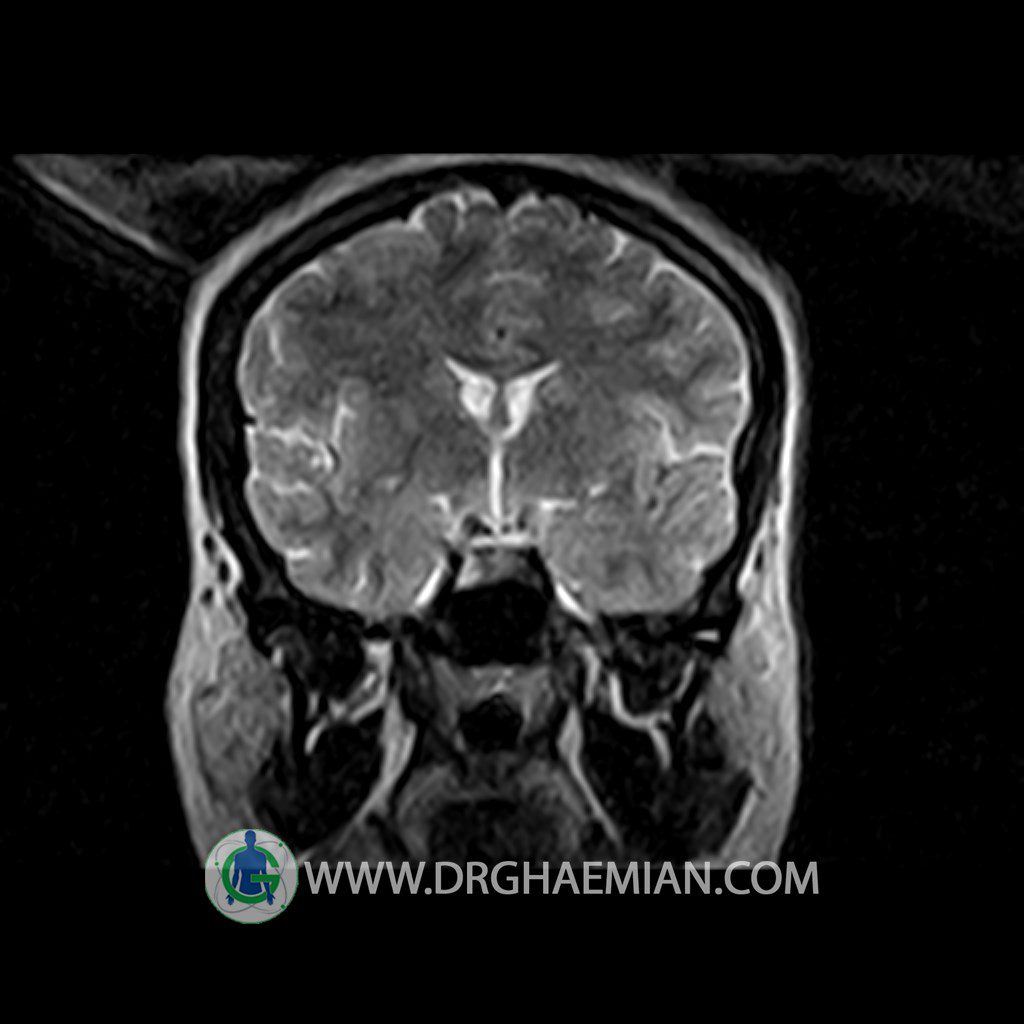

The cavernous sinus and imaged portions of the internal carotid artery and carotid siphon are unremarkable .

Evaluable portions of the neurocranium show no abnormalities .

The sphenoid sinus is clear and pneumatized .

Imaging of the hypothalamus after contrast medium administration was normal.